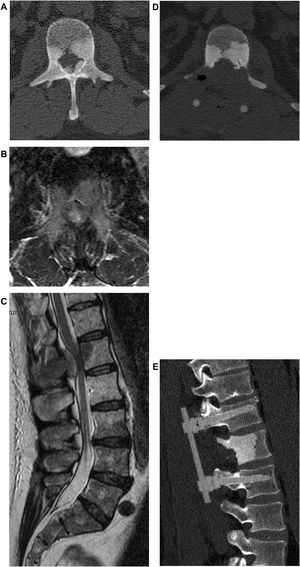

Si el paciente es considerado operable, se evalúan la extensión de la compresión de la médula espinal y la severidad del daño neurológico. De existir déficit neurológico, se evalúa la posibilidad de recuperación, sobre la base del tiempo transcurrido desde el inicio de los síntomas (figs. 2 y 3).

Varón de 58 años. Metástasis espinal en L1 derivada de cáncer de próstata con compresión de la médula espinal de tipo2 de acuerdo con la clasificación de Bilsky, con deterioro de la función neurológica en los miembros inferiores. Descompresión, citorreducción y estabilización con instrumentación PEEK reforzada con fibra de carbono mediante abordaje posterior.